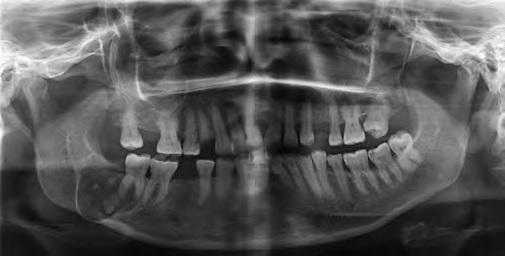

На ортопантомограмме определяется обширная рентгенопрозрачная зона, затрагивающая второй нижний моляр с правой стороны. Образование содержит кальцифицированные массы, приближающиеся к дистальному корню второго моляра, а так же несколько рентгеноконтрастных участков, расположенных на фоне зоны просветления. Данное образование являлось хорошо очерченным и вызывало выбухание и истончение костной ткани нижнего края нижней челюсти. (Фото 1).

Фото 1: Ортопантомограмма. Крупное однополостное рентгенопрозрачное образование, затрагивающее второй нижний моляр с правой стороны, с участками минерализации